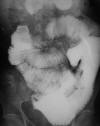

GI Differentials